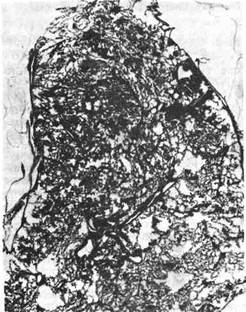

Рис. 347. Очаговый туберкулез почки.

Туберкулез почек (рис. 346, см. на цветн. вкл.) бывает обычно одно-

сторонним, клинически проявляется у молодых людей в период полового со-

зревания, а также в пожилом возрасте и реже у детей. Ранние очаги возни-

кают в корковом слое, при прогрессировании процесса очаги появляются

в сосочках пирамид; здесь начинается деструктивный процесс с образованием

полостей (рис. 347; см. рис. 346). Закрытие просвета мочеточника казеозными